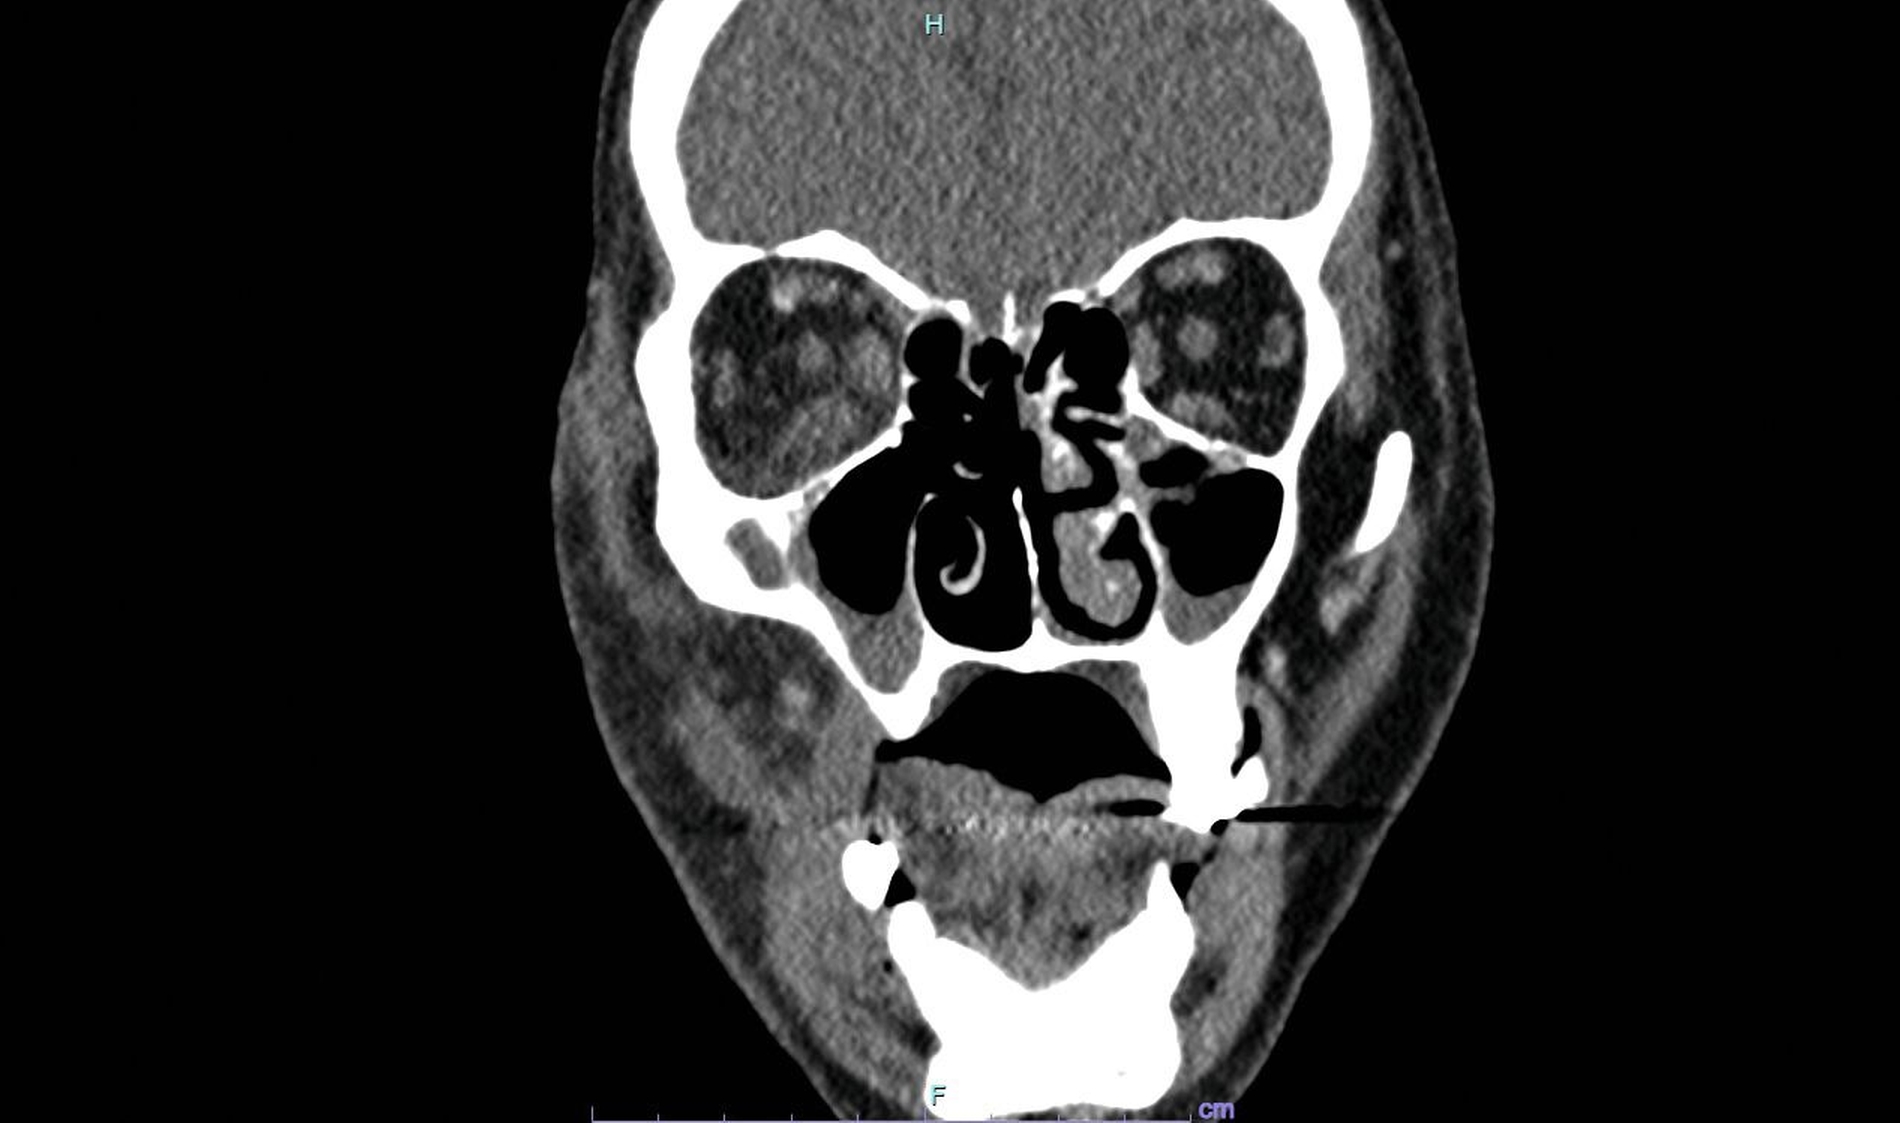

Laborchemisch offenbarte sich ein entgleister Diabetes mellitus mit einer Blutglukose von 507 mg/dl (HbA1c 11,4 Prozent) und diabetischer Ketoazidose (pH 7,15). Die Entzündungsparameter waren mit einer Leukozytenzahl von 18.000/µl und einem CRP von 30 mg/dl erhöht. Der Procalcitonin-Wert von 0,16 ng/ml sprach allerdings gegen eine bakterielle Infektion. Die Computertomografie des Schädels zeigte lediglich Resorptionen im Bereich der rechten Nasenhöhle und eine diskrete Volumenvermehrung des rechtsseitigen Wangen- und orbitalen Weichgewebes. Abszessformationen fanden sich, passend zum klinischen Befund, nicht (Abbildung 4).

Aufgrund der Dynamik dieser Erkrankung ist die schnellstmögliche Einleitung der operativen und antimykotischen Therapie entscheidend für das Patienten-Outcome. Die Computertomografie ist zwar Teil der Basisdiagnostik, aber – wie in unserem Patientenfall geschildert – nicht immer hilfreich bei der Einschätzung des Nekroseausmaßes.